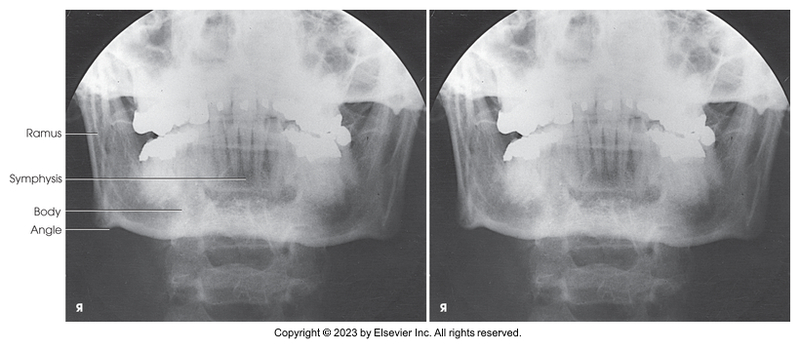

PA projection of mandibular rami

PA axial of mandibular rami

PA projection of mandibular body

PA of mandibular rami

PA axial of mandibular rami

PA of mandibular body